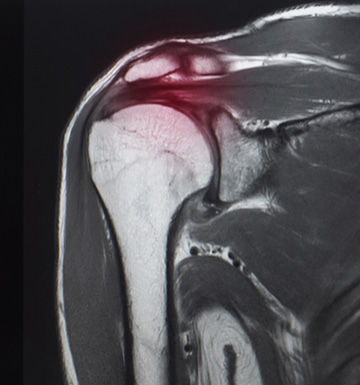

Shoulder Surgery

Why Your Rotator Cuff Tear on MRI Might Not Always Mean Surgery: What a Groundbreaking Finnish Study Means for Your Shoulder Health

As a leading shoulder surgeon in the northwest Chicago suburbs, Thomas Obermeyer MD often encounters patients worried about rotator cuff tears diagnosed via MRI. Shoulder pain is a common issue, affecting millions annually, and terms like “rotator cuff tear,”...read more